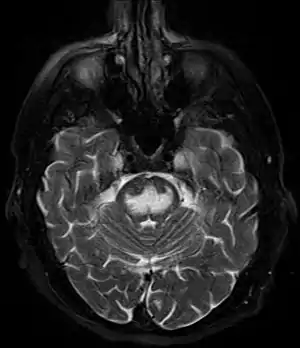

MRI image showing hyperintensity in the pons with sparing of the peripheral fibers, in a person with alcoholism and an initial serum Na of 101 who was treated with hypertonic saline, and developed quadriplegia, trouble talking, and altered mental status.

It can be diagnosed clinically in the appropriate context, but may be difficult to confirm radiologically using conventional imaging techniques. Changes are more prominent on MRI than on CT, but often take days or weeks after acute symptom onset to develop. Imaging by MRI typically demonstrates areas of hyperintensity on T2-weighted images.[27]